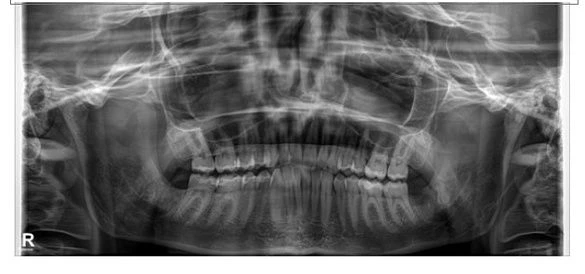

Этапы установки

На этапе подготовки к протезированию рекомендованы диагностика, лечение кариеса и заболеваний десен, а также профессиональная чистка, которые не включены в стоимость коронок Е-мах. Наши пациенты проходят обследование на современном компьютерном оборудовании, что позволяет выявить любые осложнения и противопоказания.

В большинстве случаев все этапы протезирования, включая диагностику, лечение кариозных зубов, изготовление и установку коронок Е-мах, занимают в общей сложности не более 2 недель.

- мы работаем только на сертифицированном оборудовании (внутриротовой сканер, 3D томограф, дентальный микроскоп при лечении кариеса);

Наши работы